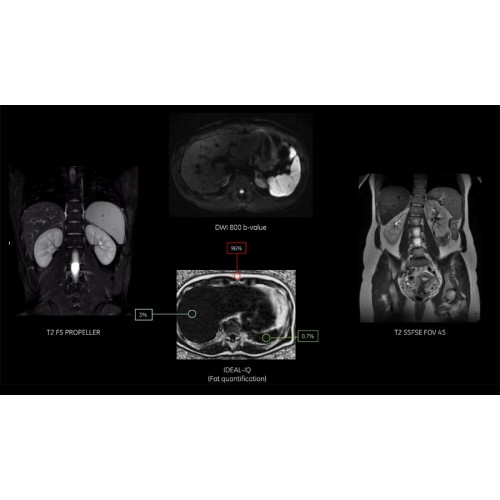

Система обеспечивает легкое сканирование, автоматическую оптимизацию протоколов, простой и автоматизированный рабочий процесс сканирования при задержке дыхания.

Снижение количества артефактов и, как следствие, уменьшение повторных сканирований.

Система SIGNA Pioneer воплощает поразительные достижения в области визуализации. Передовая технология Total Digital Imaging (TDI) позволяет добиться большей четкости изображений и на четверть повысить соотношение сигнал/шум.

• Технология Digital Surround Technology (DST) — это новая технология объемной оцифровки данных, объединяющая сигналы от каждого элемента катушки. Прекрасное соотношение сигнал/шум и чувствительность поверхностных катушек в сочетании с превосходной однородностью и высокой проникающей способностью встроенной радиочастотной катушки — все это позволяет создавать качественные изображения не только позвоночника, но и всего тела.

Технологии SIGNA Pioneer позволяют проводить полное исследование брюшной полости при свободном дыхании, минимизируя артефакты движения пациента, в том числе с МР-динамическим контрастированием.